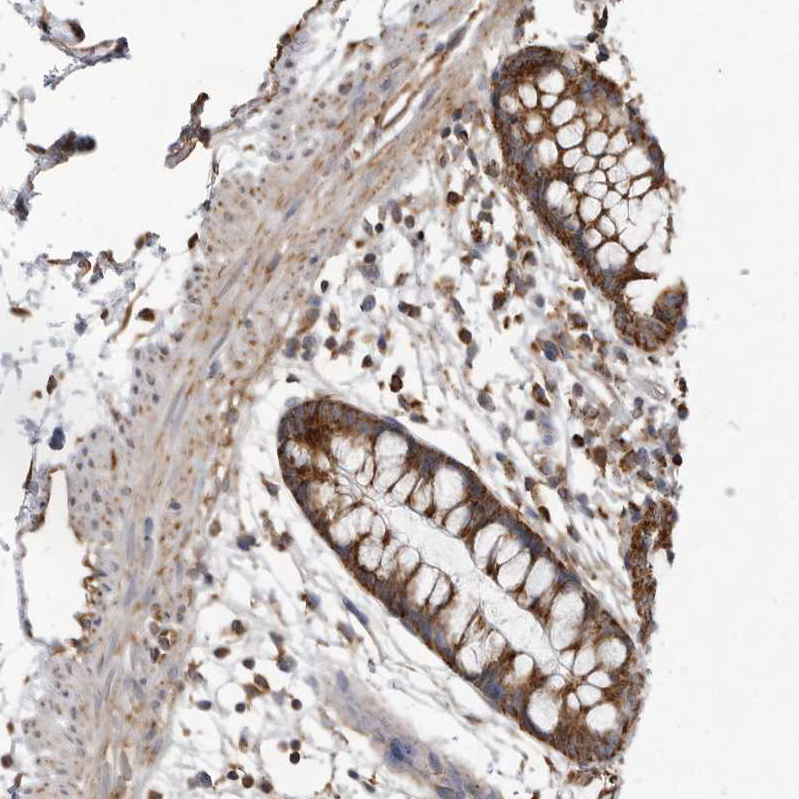

Immunohistochemical staining of human colon shows strong granular cytoplasmic positivity in glandular cells.